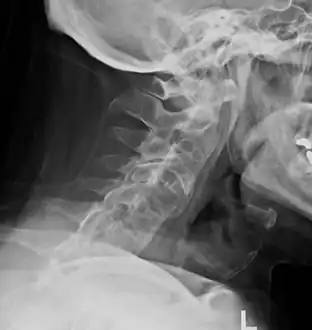

The earliest changes demonstrable by plain x–ray shows erosions and sclerosis in sacroiliac joints. Progression of the erosions leads to widening of the joint space and bony sclerosis. X-ray spine can reveal squaring of vertebrae with bony spur formation called syndesmophyte. This causes the bamboo spine appearance. A drawback of X-ray diagnosis is the signs and symptoms of AS have usually been established as long as 7–10 years prior to X-ray-evident changes occurring on a plain film X-ray, which means a delay of as long as 10 years before adequate therapies can be introduced.[21]

Lateral X-ray of the mid back in ankylosing spondylitis -

Lateral X-ray of the neck in ankylosing spondylitisImaging -